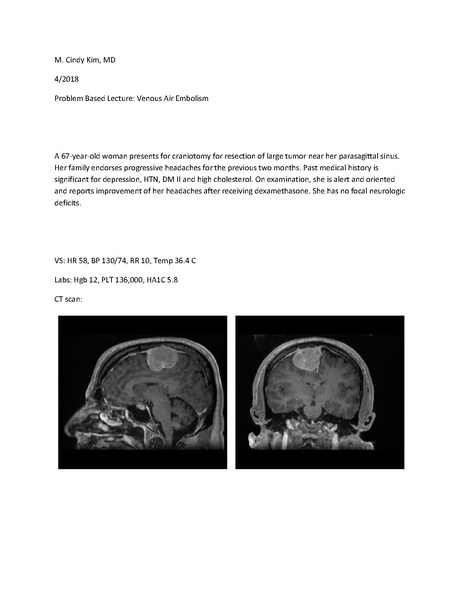

VAE Lecture By Cindy Kim